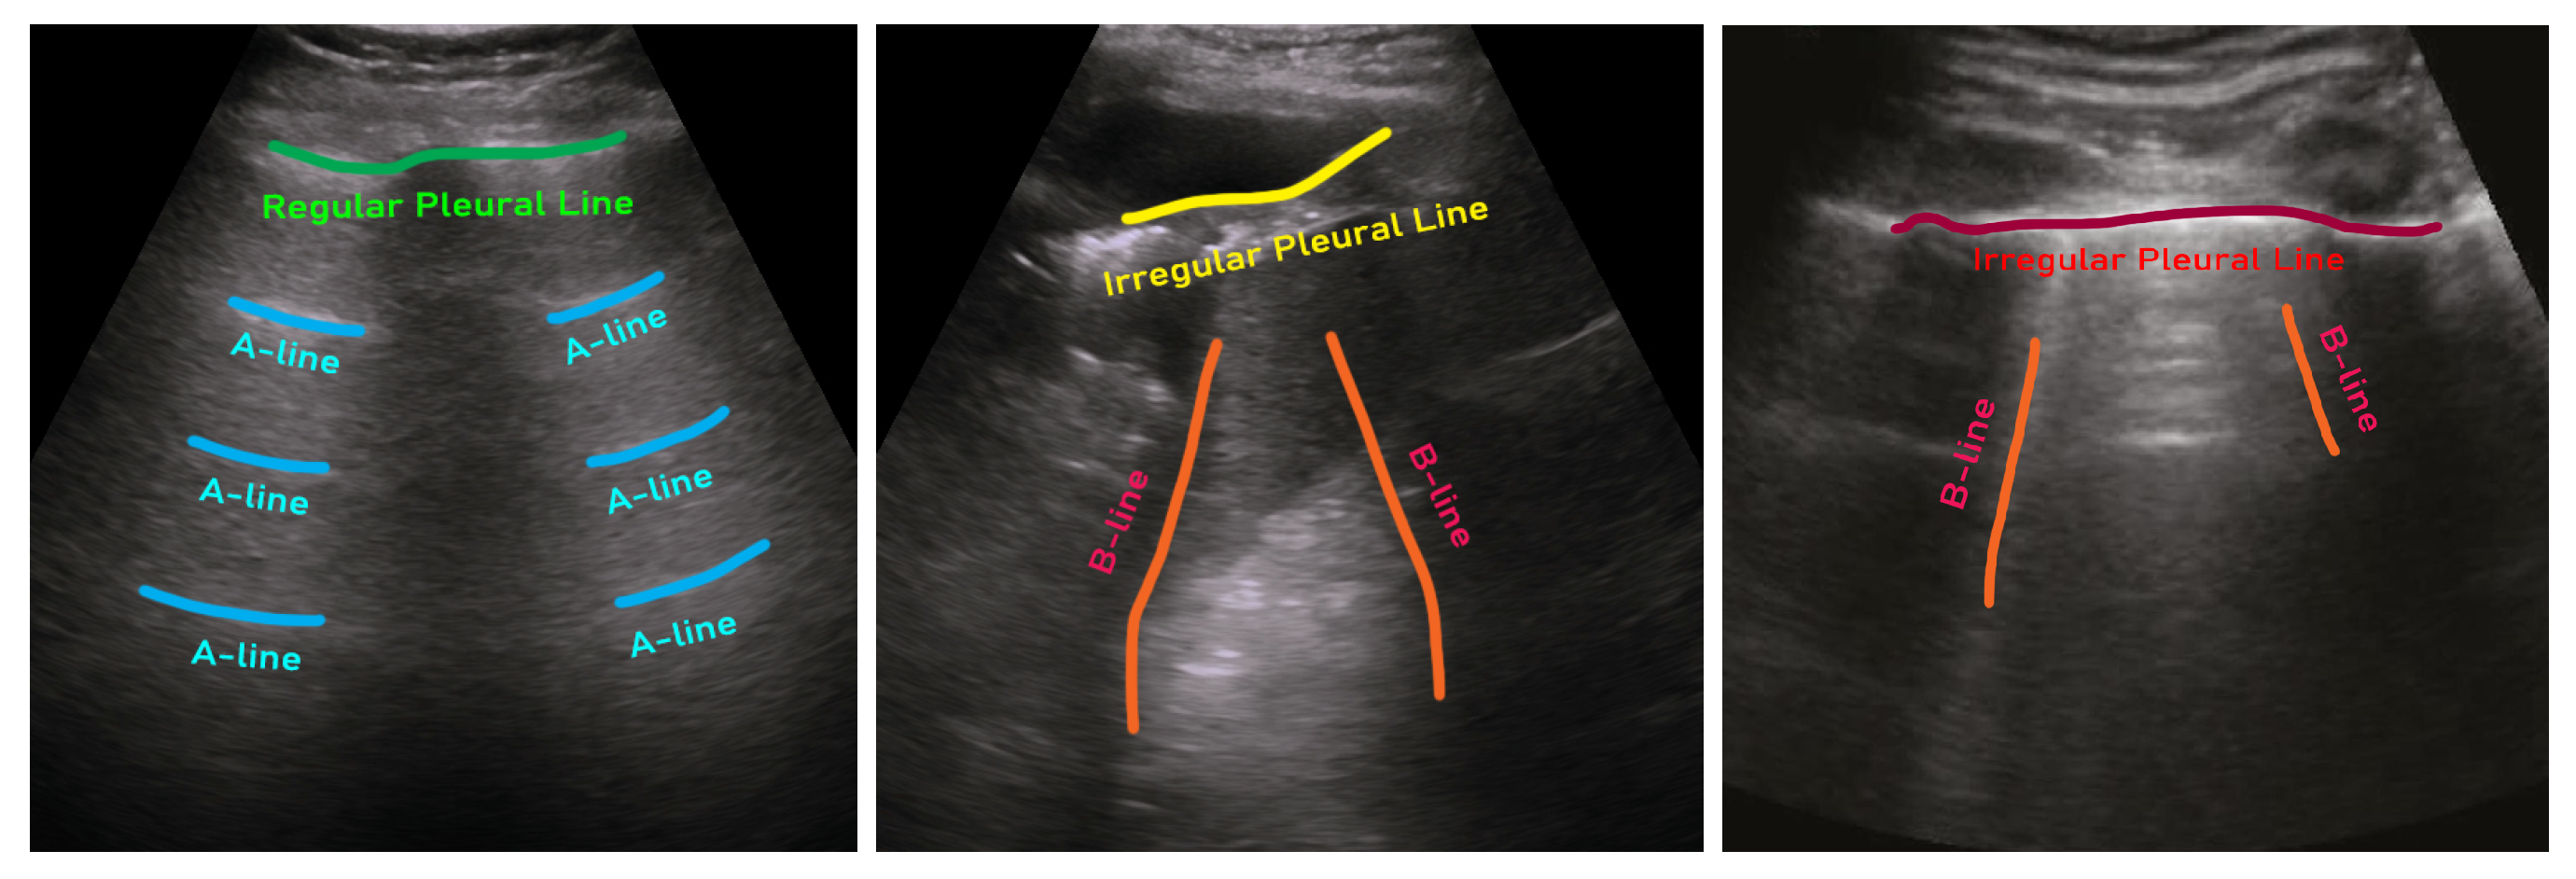

- Soldati, G.; Demi, M.; Smargiassi, A.; Inchingolo, R.; Demi, L. The role of ultrasound lung artifacts in the diagnosis of respiratory diseases. Expert Rev. Respir. Med. 2019, 13, 163–172. [Google Scholar] [CrossRef]

- Soldati, G.; Smargiassi, A.; Inchingolo, R.; Buonsenso, D.; Perrone, T.; Briganti, D.F.; Perlini, S.; Torri, E.; Mariani, A.; Mossolani, E.E.; others. Proposal for international standardization of the use of lung ultrasound for patients with COVID-19: A simple, quantitative, reproducible method. J. Ultrasound Med. 2020, 39, 1413–1419. [Google Scholar] [CrossRef] [PubMed]